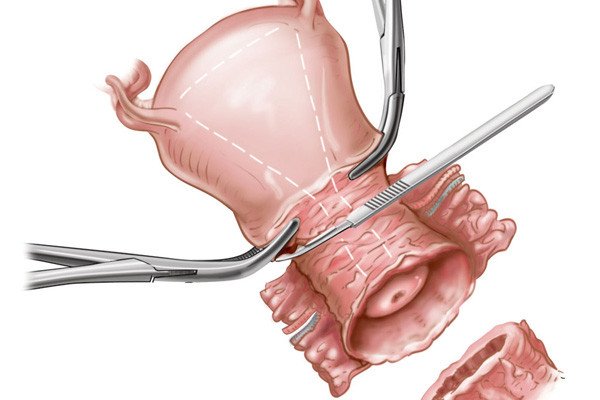

In a recent study in the journal cancer epidemiology, biomarkers and prevention had found that women who. Cryosurgery this treatment kills the cancer cells by freezing them. Ad learn more about a treatment option for advanced cervical cancer.